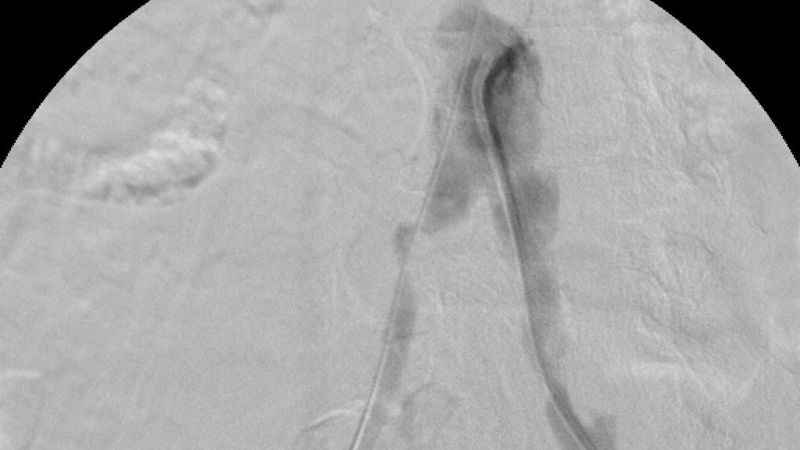

Türkiye’nin ilk yerli stent grefti başarıyla hastalara uygulandıINVAMED'in geliştirdiği "Atlas Stent Greft", Bezmiâlem Vakıf Üniversitesi Tıp Fakültesi'nde gerçekleştirilen başarılı operasyonla hastalara uygulandı.

Özellikle anjiyografik yöntemlerle ameliyat gerektirmeden tedavi olanağı sunuluyor. Balon, stent ve damar tıraşlama yöntemleri, bu tedavilerin başında geliyor. Bu tedavilerde kullanılan tıbbi cihazların üretimi bir zamanlar yalnızca belirli ülkeler tarafından yapılırken, artık Türkiye kendi cihazlarını üreterek dünya sahnesinde yer alıyor. Bu alanda yaşanan en büyük yeniliklerden biri de "stent greft" teknolojisi oldu. Üretimi dünyada sadece 5 ülke tarafından yapılan stent greft üretimi ile Türkiye, tıbbi inovasyon alanında tarihi bir başarıya imza attı. Bu büyük adım Türkiye'nin sağlık teknolojilerindeki gelişimini küresel arenada da tescilledi.

Türkiye'nin ilk yerli stent grefti Bezmiâlem Vakıf Üniversitesi Tıp Fakültesi'nde Prof. Dr. Cengiz Köksal ve Doç. Dr. Emre Selçuk'un öncülüğünde Artven koordinasyonuyla bir hastaya başarıyla uygulandı. Doç. Dr. Emre Selçuk, bu büyük adımı şöyle değerlendirdi:

"Stent-greft teknolojisi, damar tedavilerinde kritik bir rol oynuyor. Damar balonlaşması veya yaralanma riski olan hastalarda bu teknolojinin önemi daha da artıyor. Artık bu teknolojiyi Türkiye'de üretiyor olmamız, operasyon başarımızı artırmanın yanı sıra, hasta güvenliğini de üst seviyelere taşıyacaktır. Türkiye'nin tıbbi alandaki bu başarısında yer almaktan büyük gurur duyuyoruz. Atlas Stent Greft, Türk mühendisliğinin ve Türk doktorlarının inovasyonunun ne kadar ileri seviyede olduğunun bir göstergesidir."